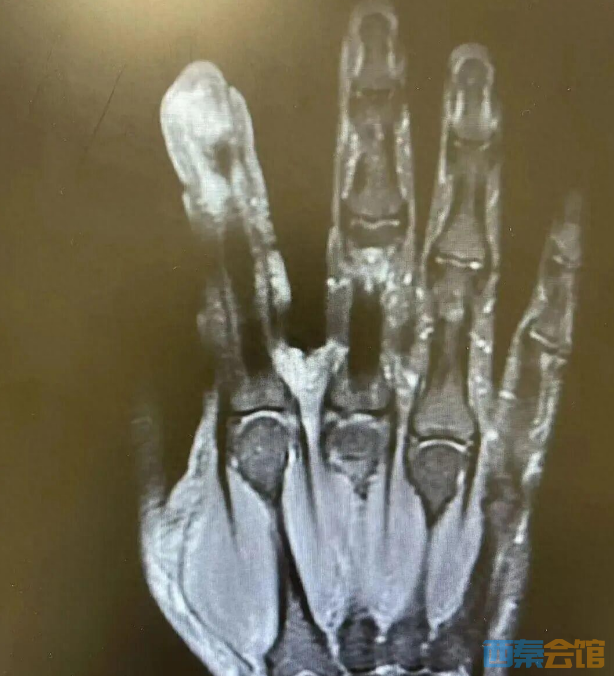

经检查,李大哥破溃的左手指尖严重感染,厌氧消化链球菌顺着破损处钻到骨头里,引发了严重骨髓炎。医生紧急手术,帮李大哥“刮掉”坏死的骨头碎片,清除了坏死的肌肉与皮肤。